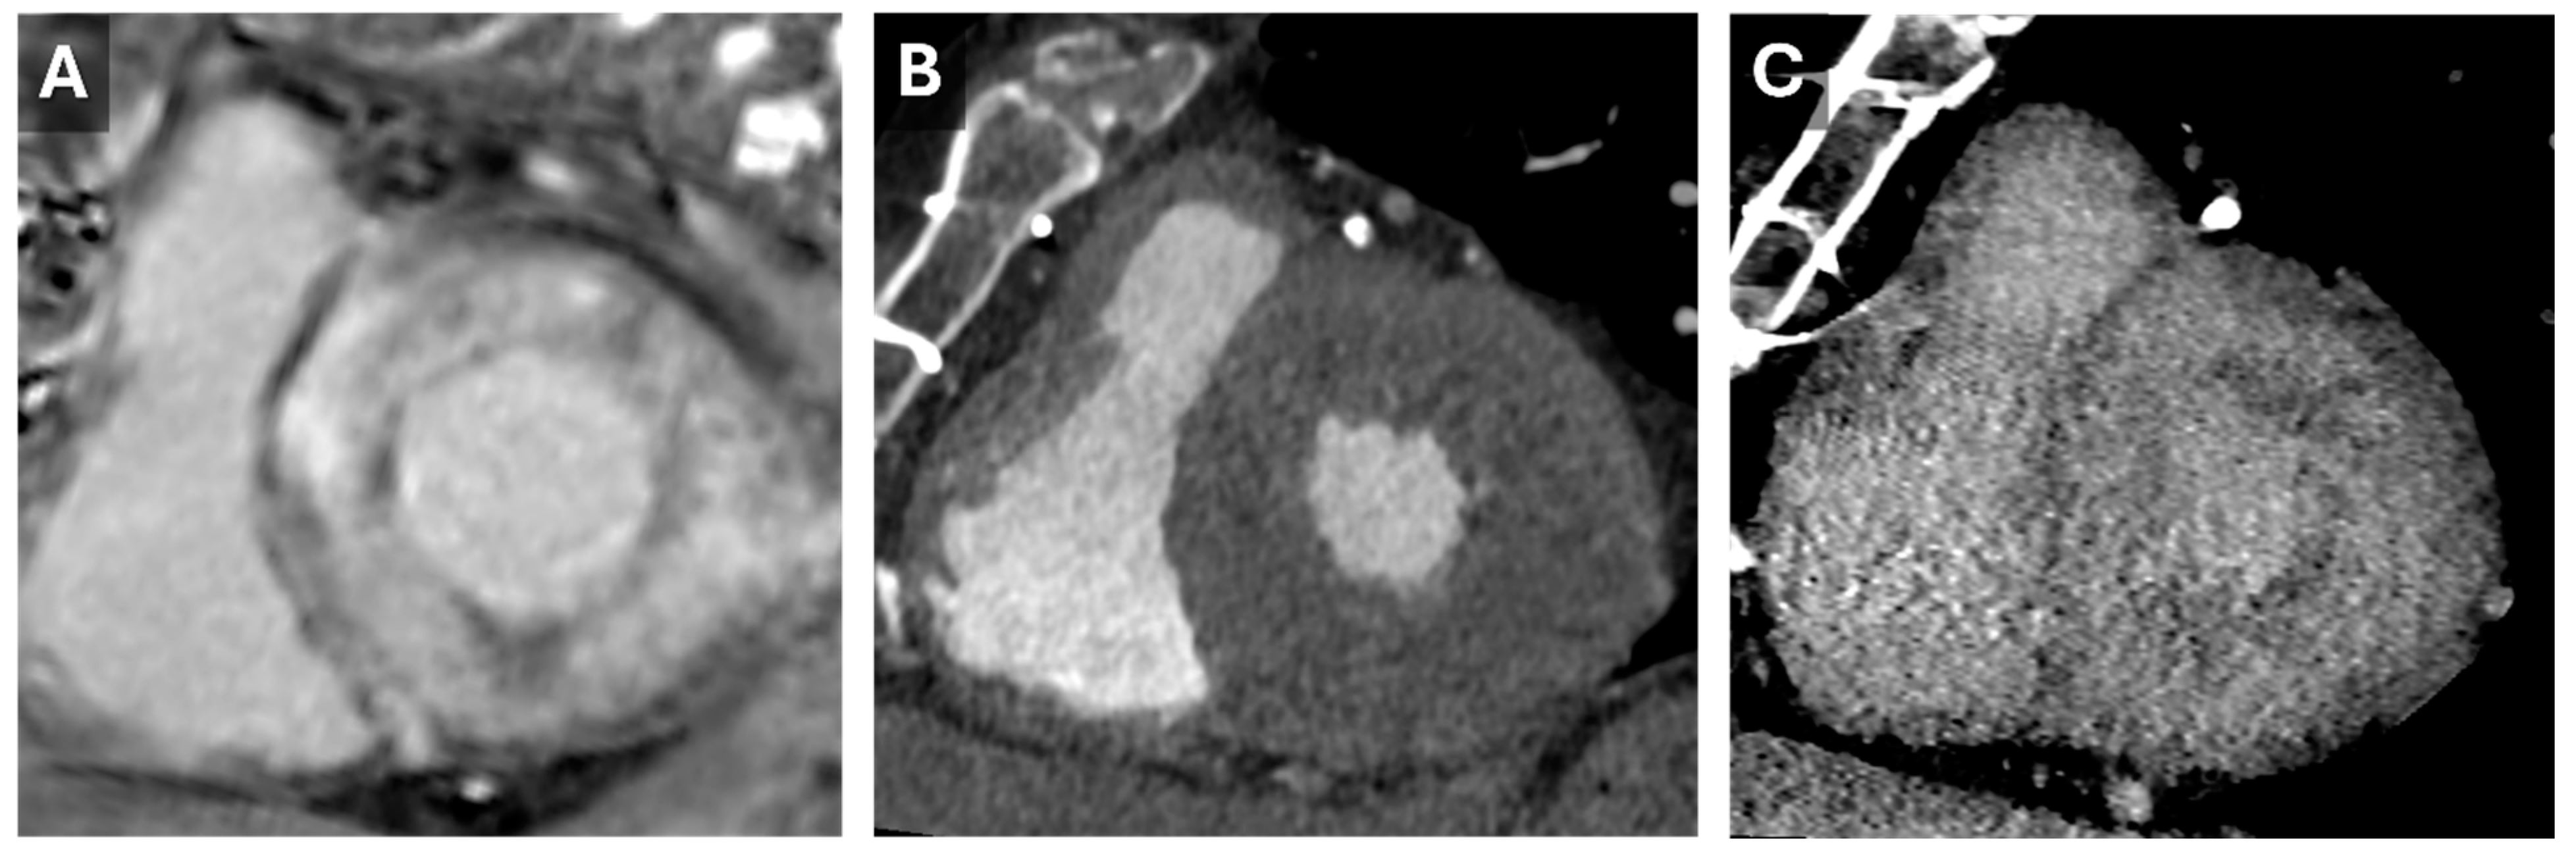

Figure 5.

Cardiac Amyloid Findings. CMR short-axis delayed-enhanced inversion recovery image through the LV base (A) from a patient with severe cardiac amyloidosis with diffuse transmural delayed enhancement. Short axis images through the LV base from a previous cardiac CT with arterial (B) and 5 min delayed (C) phases. The delayed phase demonstrates diffuse nonvascular enhancement that correlates well with the findings seen on the subsequent CMR.

Despite its advantages, CT for ECV measurement has limitations, including a low signal-to-noise ratio and the need for higher contrast doses. Dual-energy CT can address some of these issues by reducing contrast requirements and utilizing varying tube potentials (Figure 6) [26]. This approach was validated in 2020 when Ohta et al. demonstrated a significant correlation between CT- and CMR-based ECV quantification in 23 patients [32].

Figure 6.

Dual-energy Cardiac CT Imaging. Short-axis reconstructions through the LV base from a 5 min delayed phase of a contrast-enhanced cardiac CT that utilized spectral (dual energy) technique. Images from the high-energy (A) and low-energy (B) datasets show the increase in iodine conspicuity from the low-energy data (B). A virtual monoenergetic 50 keV reconstruction (C) demonstrates a good mix of anatomic information and contrast conspicuity.